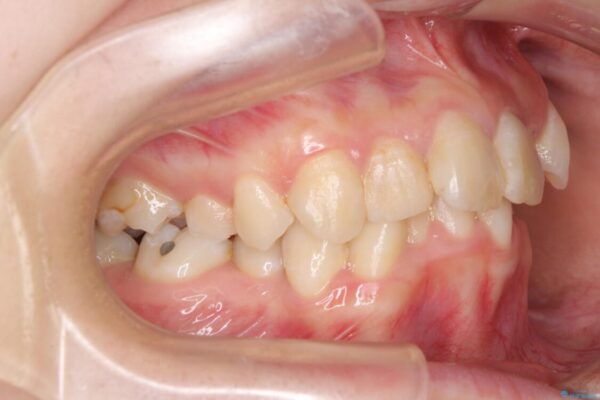

内側に倒れ込んだ歯や下の前歯が隠れてしまうほどの咬み合わせを改善したいとのことで来院された患者様です。

治療前

• デコボコと深い咬み合わせ ワイヤー装置での抜歯矯正 治療前画像